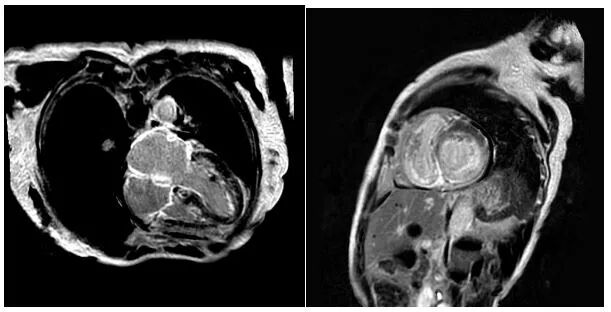

随后,该患者前往厦心就诊,通过心电图,心脏磁共振、心脏超声心肌应变力检测等检查,需要考虑的可能性诊断:浸润性心肌病。其中,最常见的是心肌淀粉样变性(Amyloid cardiomyopathy, CA)。经过一系列的血液和影像学检查,病人诊断为甲状腺素运载蛋白淀粉样心肌病(transthyretin amyloid cardiomyopathy, ATTR-CA)。当看到典型的心电图低电压和原因不明的心肌肥厚的超声改变,应该高度怀疑淀粉样心肌病。医生高度怀疑为“心肌淀粉样变”。

心脏磁共振(CMR)提示左右心室心肌增厚合并心内膜下弥漫性的纤维化病变

本文中的这位患者,后来又做了心脏磁共振(CMR)提示左右心室心肌增厚合并心内膜下弥漫性延迟强化,轻链检测阴性。为了进一步分型,血液被送检,检测到异常单克隆免疫球蛋白。接着病人做了99锝焦磷酸盐(99m Technetium-pyrophosphate)核素扫描。这项检查对ATTR 淀粉样变性的特异性可以高达97%。结果显示该患者的心脏呈强阳性改变。根综合该患者临床及检查结果,ARRT的诊断明确。为进一步分型,进行基因检测,检测出至ATTR的但基因突变,故该患者最终诊断突变型ATTR明确。该患者的弟弟也进行了D-SPECT扫描及基因检测,最终诊断突变型ATTR,其突变位点与其姐姐一致。